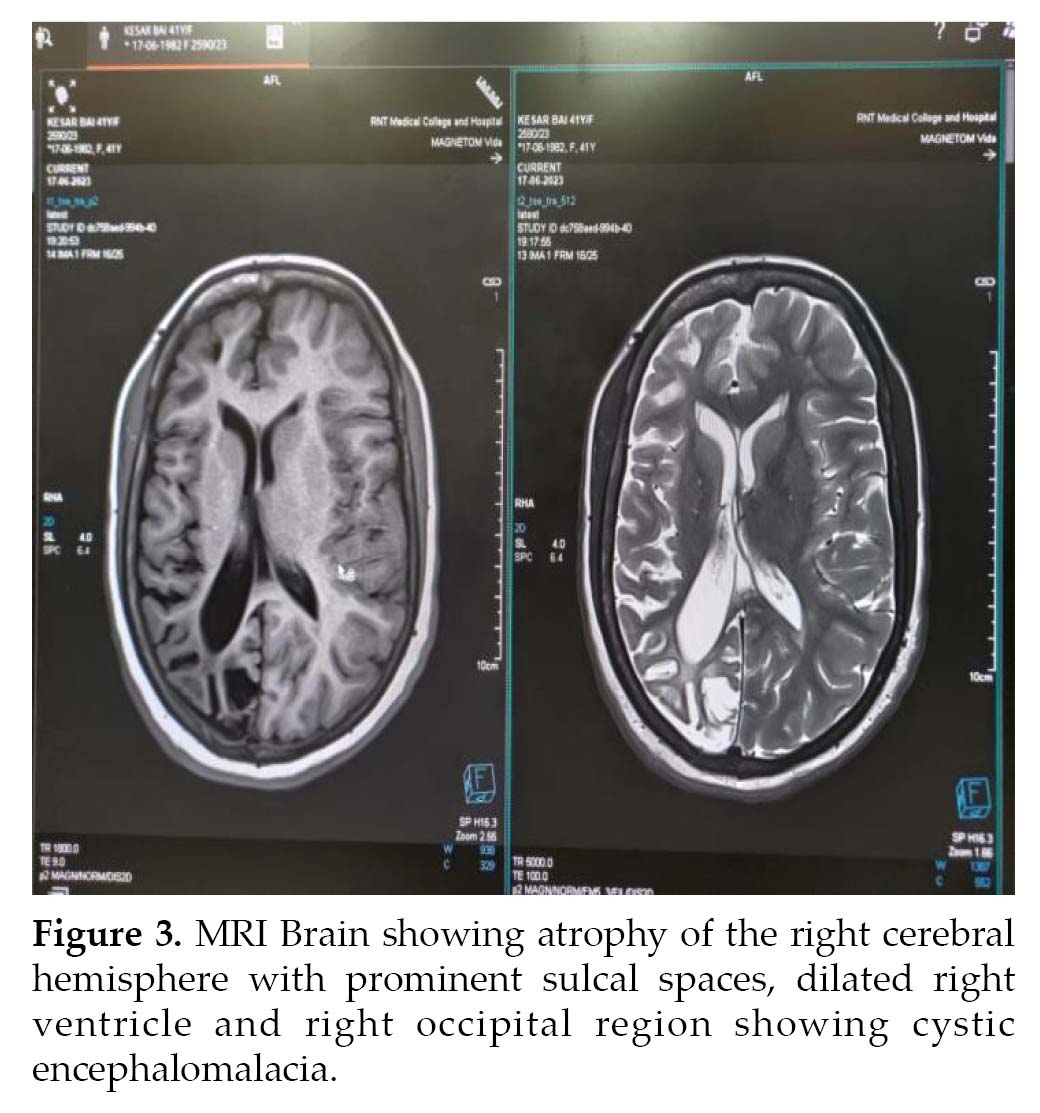

Noncontrast computed tomography (NCCT) (Fig. 2) head and MRI (Fig. 3) brain was performed, which revealed atrophy and prominent sulci and gyri of right cerebrum and cerebellum, with dilation of right lateral ventricle. There was mild cortical hyperostosis on the right side compared to the left. Nonpneumatization of left frontal sinus with enlarged right frontal sinus was seen. The left occipital region showed cystic encephalomalacia. EEG revealed epileptiform discharges in the form of paroxysmal generalized spike and wave having amplitude of 100-200 µV. Histopathology could not be done as the attendants were not willing. The patient was treated with tablet phenytoin 300 mg HS and tablet valproate 500 mg BD.